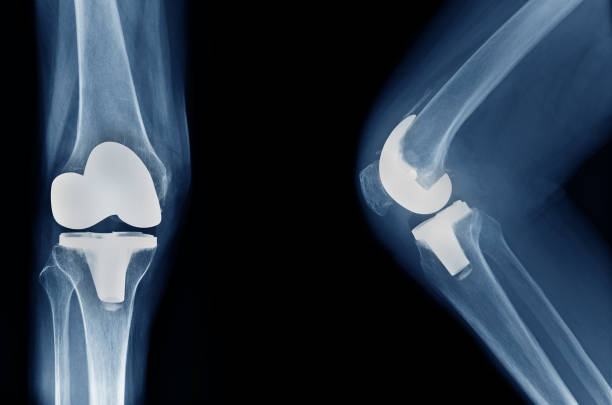

Advanced Joint Replacement Surgery in Noida

When it comes to joint replacement surgery, ShardaCare – Healthcity is your trusted partner. We offer expert Knee Replacement Surgery, Hip Replacement Surgery, and Ankle Replacement Surgery in Noida to help you regain your mobility and reduce pain. Our highly skilled surgeons use advanced techniques to perform joint replacements, minimising downtime and accelerating recovery.

From joint replacements to fracture repairs and spinal fusion, orthopaedic surgery addresses a range of musculoskeletal conditions, restoring function and mobility.